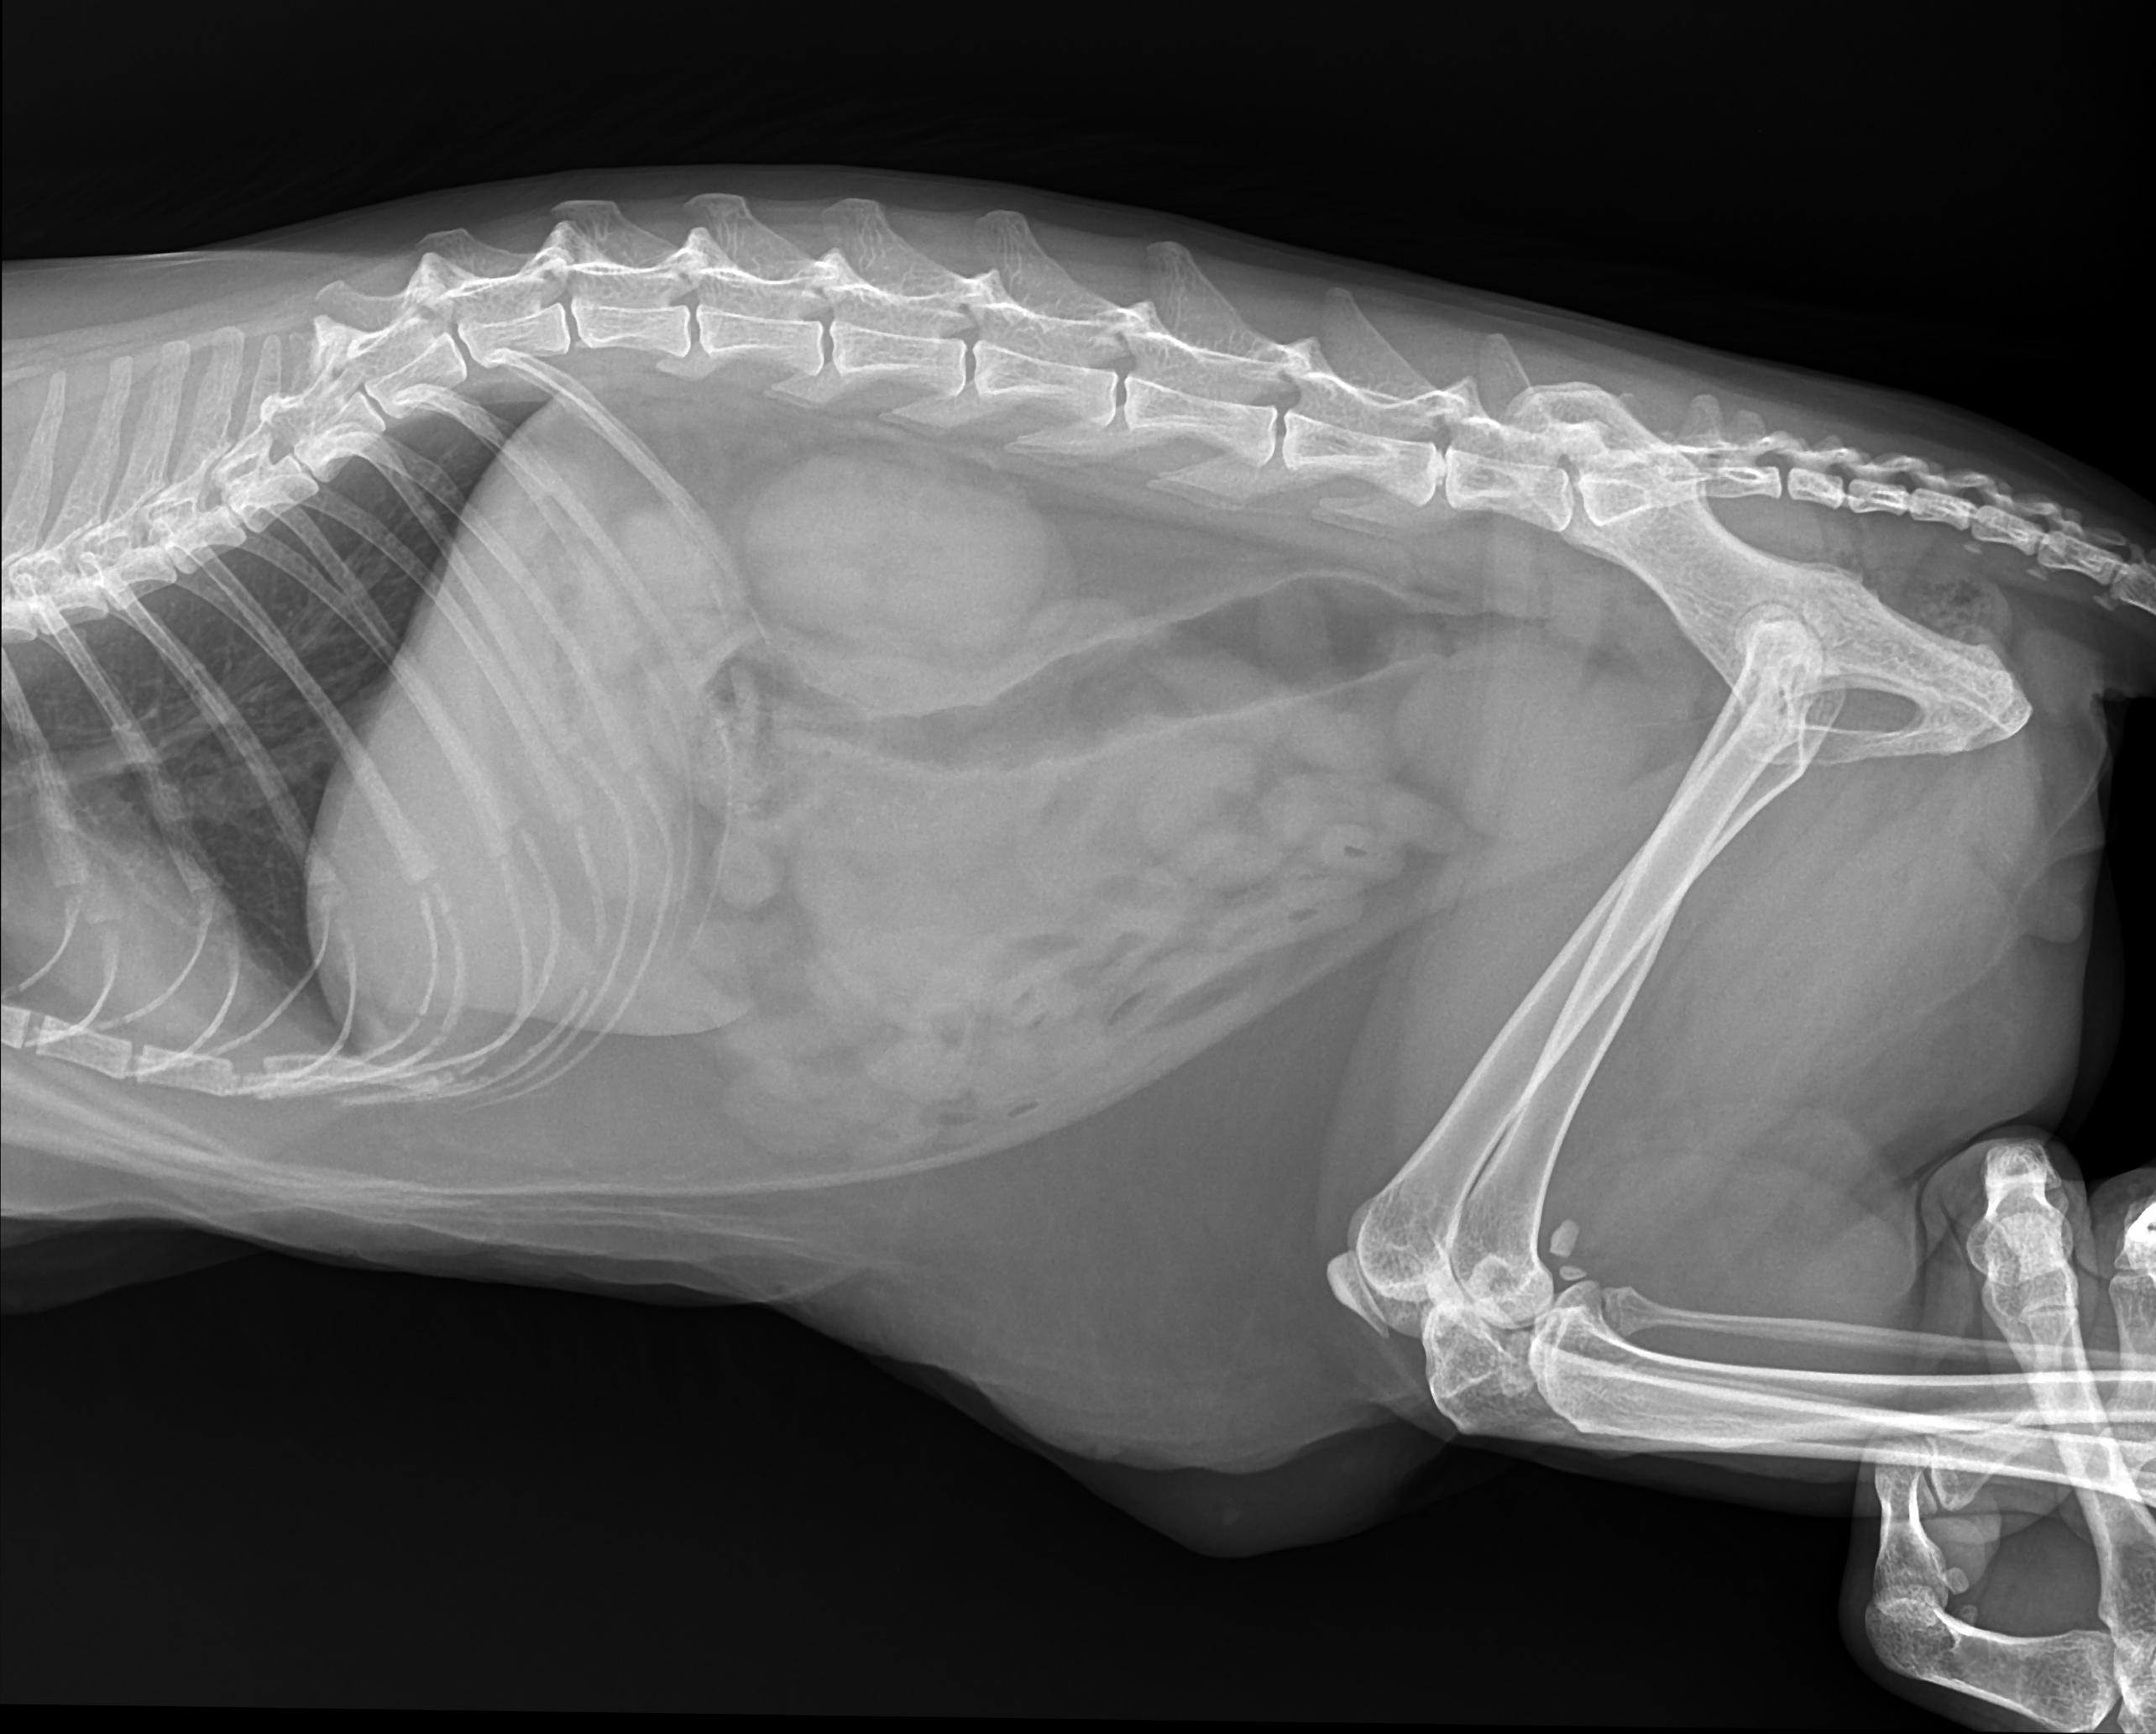

Рентгеновские снимки анатомии собак: строение и здоровье